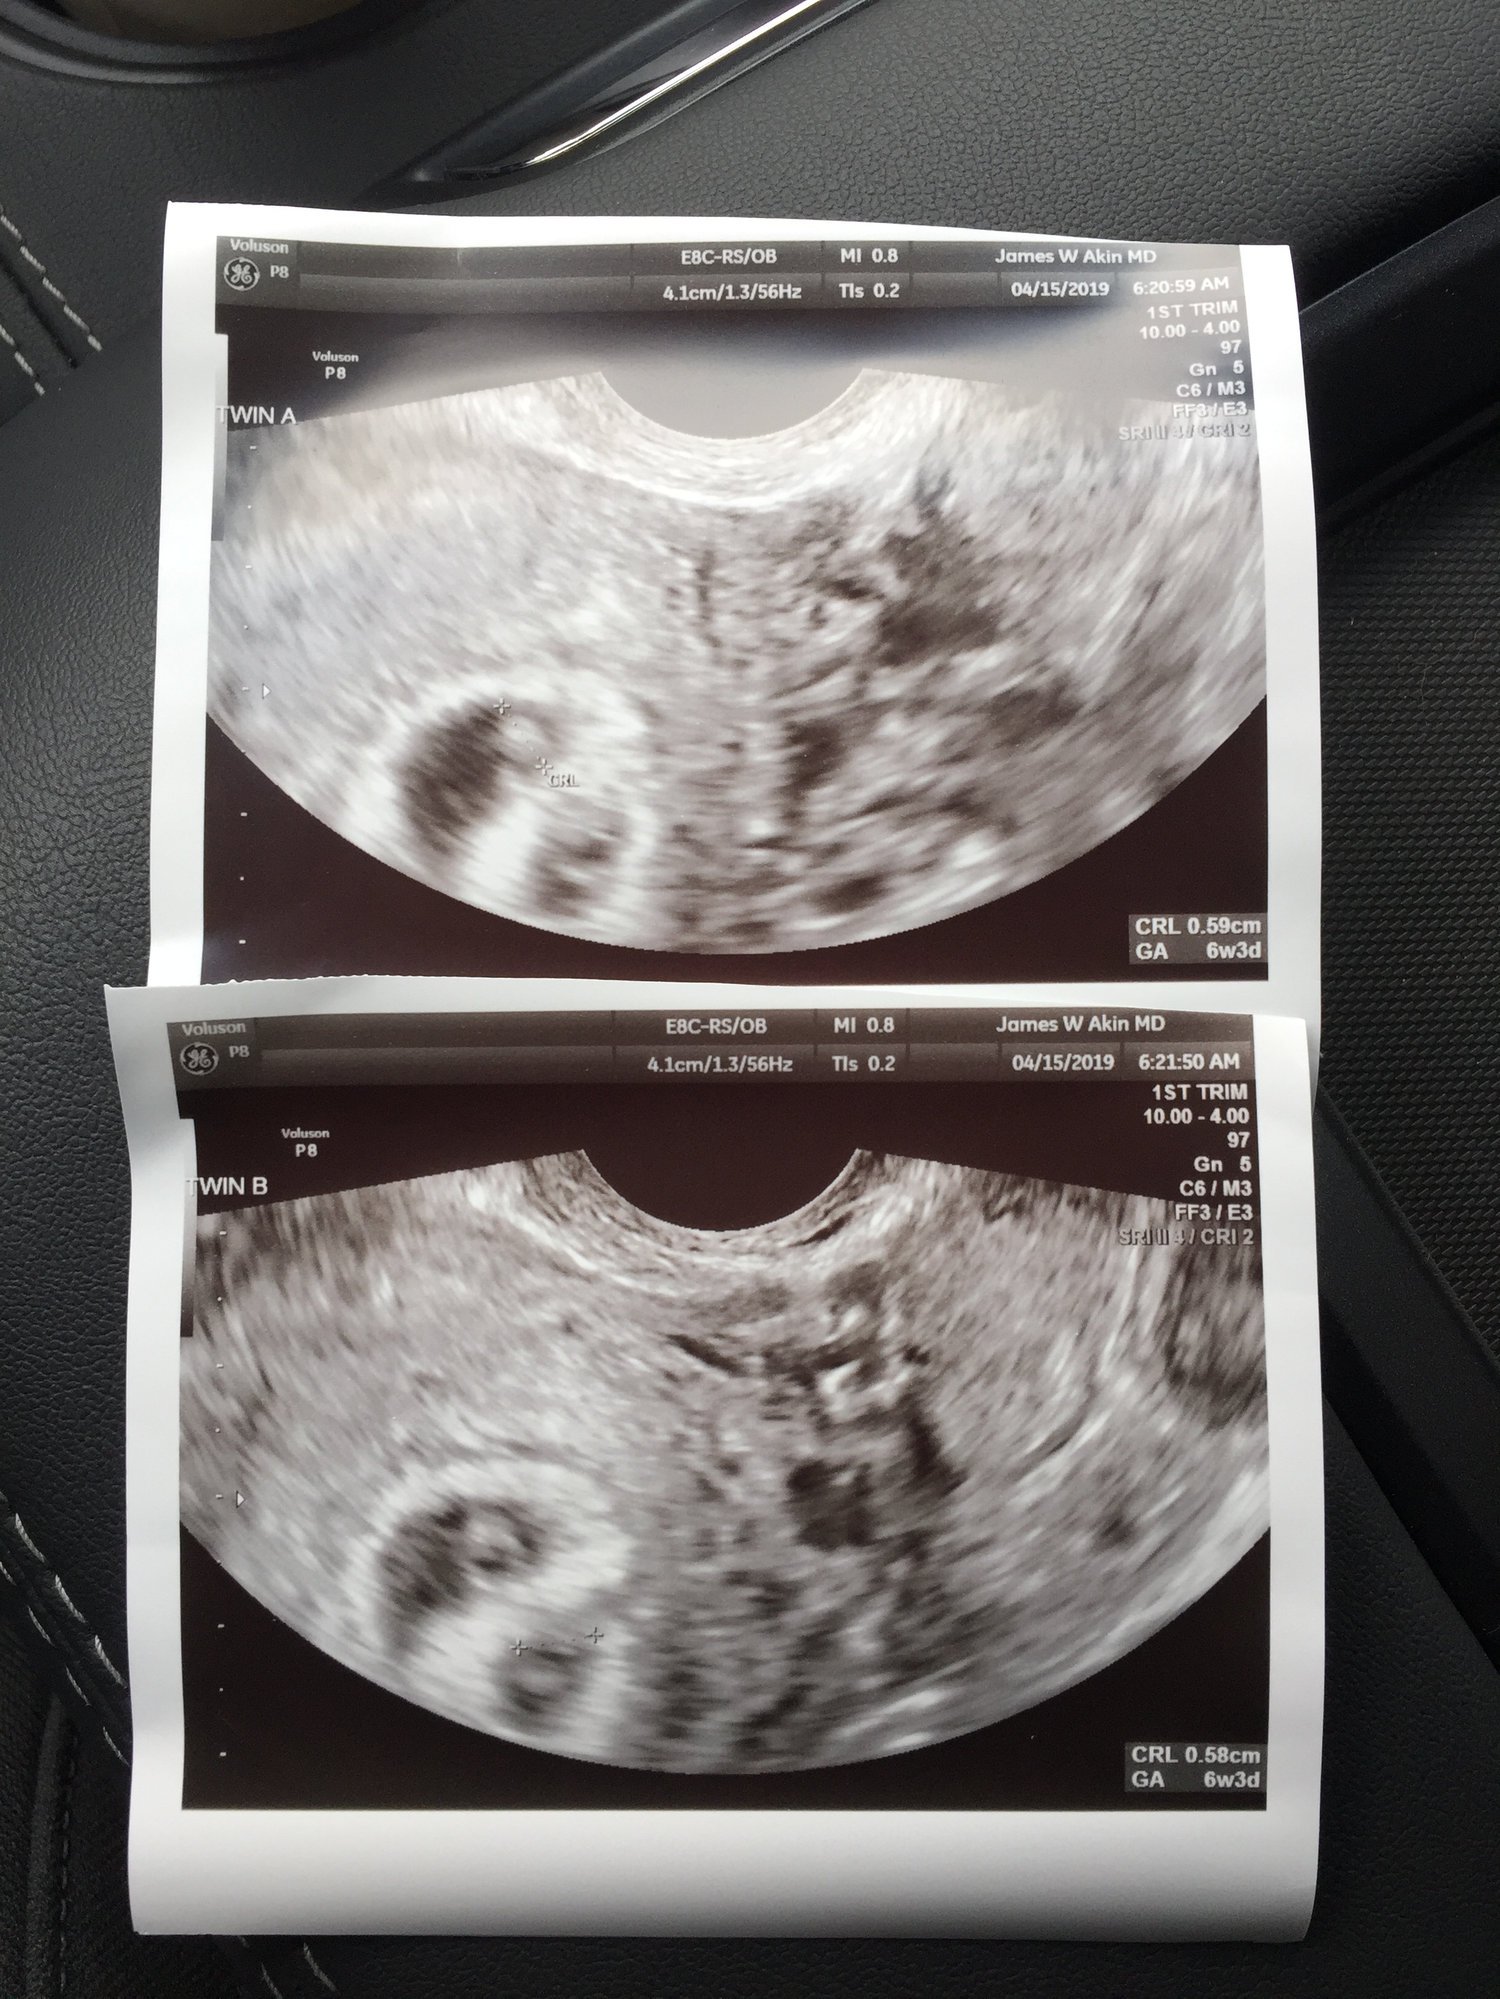

Twin A and Twin B both look good! Both measuring at 6w3d and have good looking heartbeats. We’ll be able to hear them on the 29th 😍